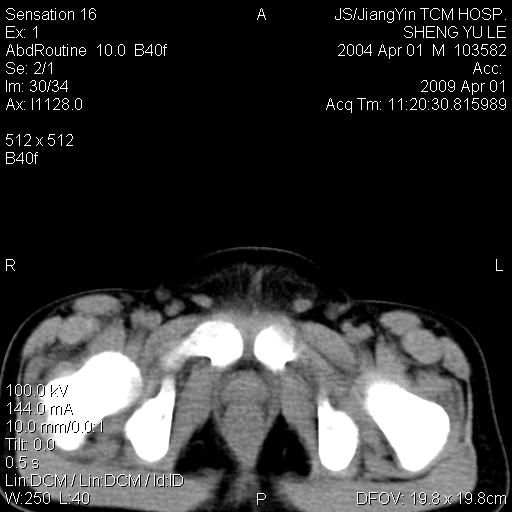

m,5岁。尿痛尿频数天。既往无病史。ct平扫腹盆腔积液。膀胱壁明显增厚。另可见心包增厚。wbc5万,骨髓穿等结果。请指教。

膀胱影像表现结合临床应该是急性膀胱炎症,但为什么有腹水呢?双肾输尿管无扩张,泌尿系压力应该不大不至于引起尿外渗,应该是腹膜感染引起的,但楼主没有提及相关症状,腹膜及膀胱结核?患者白细胞5万(结核不至于这么高啊),脾脏增大,是不是有白血病?进一步检查。。

腹水,膀胱壁增厚,wbc5万,结合临床,支持感染性疾病---感染性腹膜炎、腹水,急性膀胱炎,败血症。期待结果。